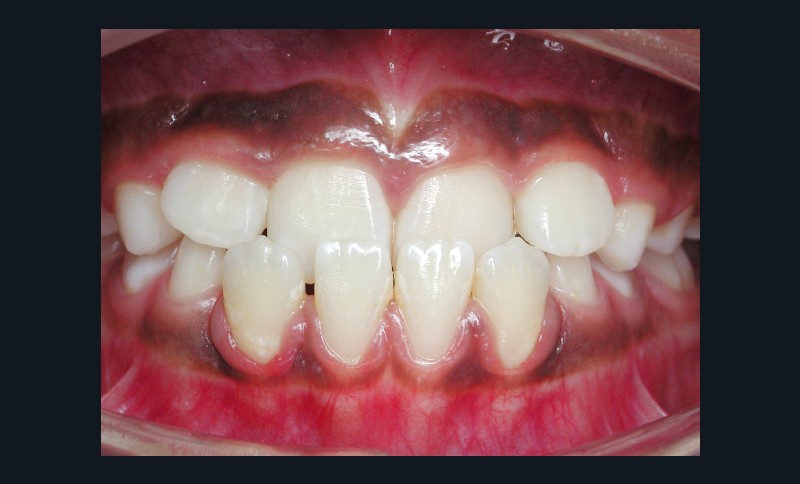

L’omnipraticien est très souvent confronté à cette question lors de sa pratique quotidienne : quel est le bon moment pour adresser les enfants chez l’orthodontiste ? La réponse peut recéler quelques difficultés, car elle est spécifique à chaque enfant. Le temps où il était conseillé d’attendre la denture définitive pour intervenir est révolu : certaines interventions précoces permettent aujourd’hui dans certains cas de raccourcir et de simplifier les traitements orthodontiques. C’est notamment le cas des anomalies transversales, qui sont celles qui sont traitées le plus précocement, dès 6 ans. Ainsi, lors d’anomalie cliniquement évidente, la consultation orthodontique s’impose. Cependant, certaines anomalies sont plus discrètes, et donc plus difficiles à dépister. Une panoramique doit toujours être réalisée en première intention afin de dépister les agénésies. Puis, même en l’absence d’anomalie évidente, il est recommandé d’adresser les enfants chez l’orthodontiste entre 7 et 9 ans : celui-ci sera ainsi à même d’adapter la prise en charge, et surtout l’âge idéal de prise en charge pour chaque patient(fig. 3 et 4).